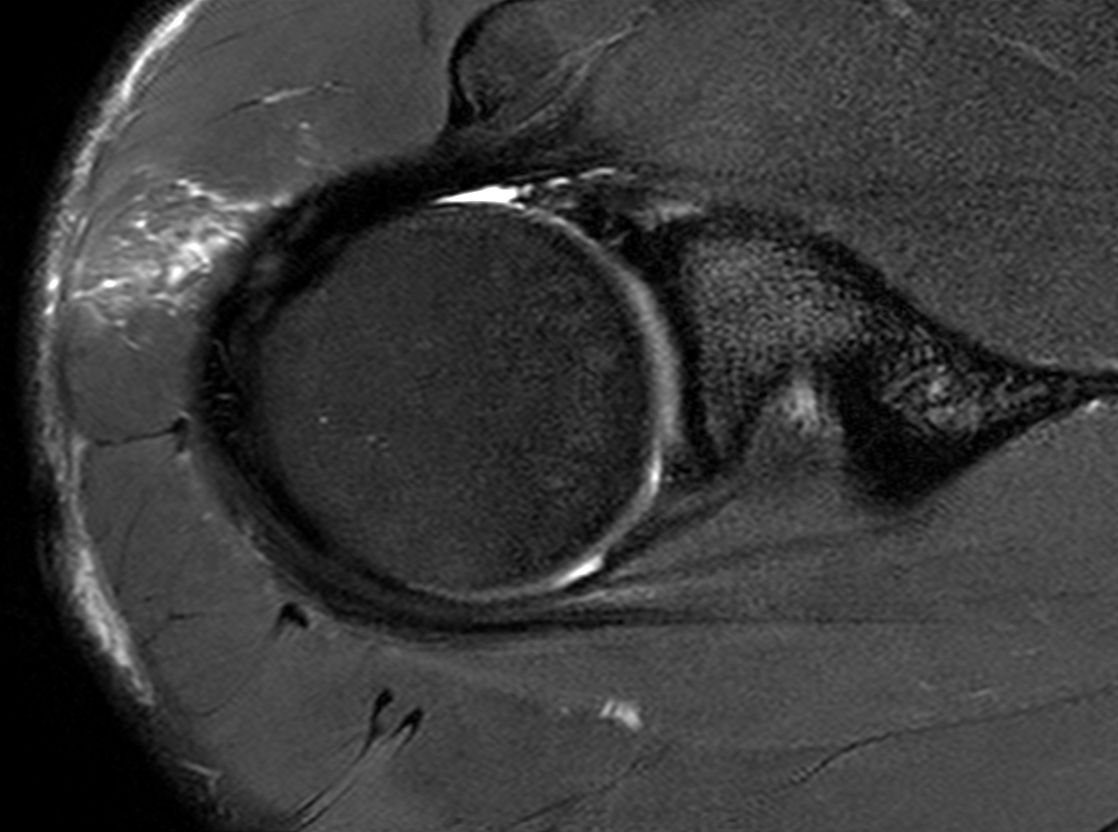

Axial T2w SPAIR